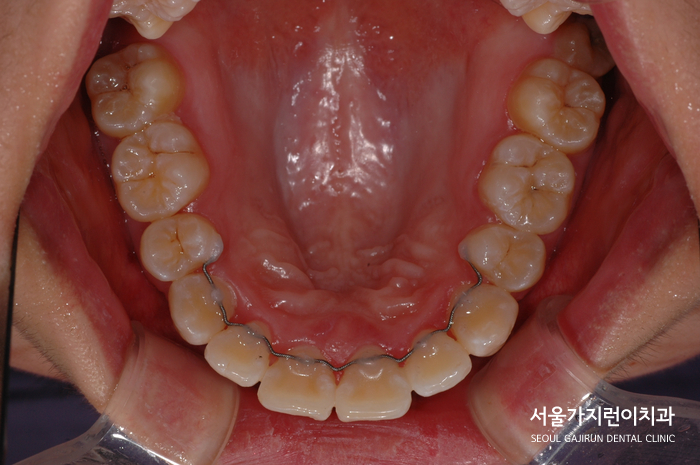

교정이 완료된 이후 모습인데요. 정중선도 맞는 모습을 볼 수 있고 좌우 교합의 균형도 잘 맞아 편측 저작 우려도 해소된 모습을 볼 수 있었어요. 무엇보다 치아의 각도가 제대로 세워지면서 교합선도 자연스러워지고 돌출감도 많이 개선이 되었는데요. 이후 환자분이 집중해줄 부분은 고정식 유지장치를 사용했기 때문에 유지장치 주변으로 치석이 쌓이지 않도록 관리해 주는 것이에요.